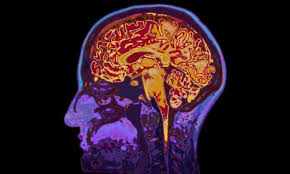

Imagine if we could reduce the risk of dementia the same way we reduce the risk of skin cancer—with a simple, catchy public health campaign like “Slip, Slop, Slap.” That’s exactly what renowned brain health expert Professor Henry Brodaty is calling for. In his address at the National Press Club this week, Prof Brodaty made a compelling case: Australia needs a nationwide dementia prevention campaign that tackles modifiable risk factors head-on.

Professor Brodaty, co-director of the Centre for Healthy Brain Ageing (CHeBA) at the University of New South Wales, says the nation is underestimating what’s possible when it comes to dementia. Drawing a powerful comparison to Australia's success in campaigns against smoking and sun-related cancers, he stressed that dementia should be no different—especially since nearly half of the known risk factors are within our control.

He painted a hopeful picture: imagine a population actively improving their diets, staying mentally and socially engaged, managing blood pressure and cholesterol, and exercising regularly—not just for physical health, but to protect the brain. He emphasized that this isn’t about futuristic treatments or costly drugs. It’s about using the tools we already have to delay the onset of dementia and reduce its overall impact.